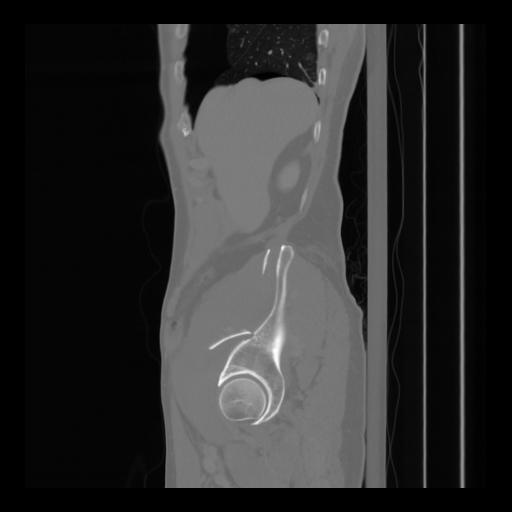

36 CUERPO,CE,Sagittal,3.000,CUERPO,Sagittal,